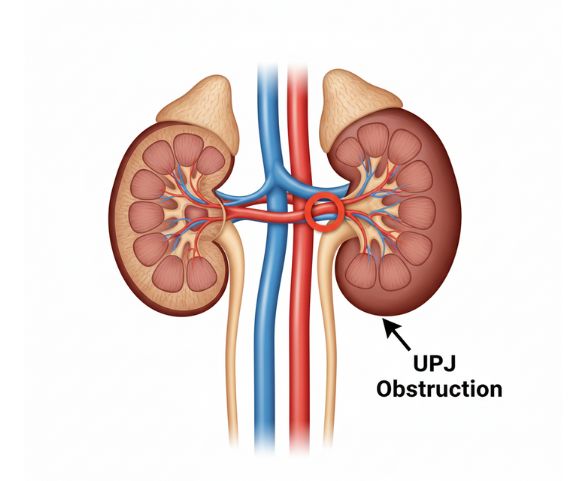

A UPJ obstruction (Ureteropelvic Junction Obstruction) is a blockage at the junction where the kidney meets the ureter, which restricts the normal flow of urine from the kidney to the bladder. This condition can be present from birth or develop later due to scarring, compression from nearby blood vessels, stones, or inflammation. When left untreated, UPJ obstruction may lead to kidney swelling (hydronephrosis), pain, recurrent urinary tract infections, or reduced kidney function.

UPJ obstruction occurs when a blockage at the ureteropelvic junction prevents urine from flowing normally from the kidney to the ureter. This leads to urine buildup in the kidney (hydronephrosis) and may affect kidney function over time. The main causes include: